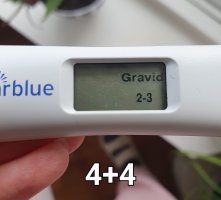

4+4

I dag har jeg vært hos legen og tatt hcg prøve nummer to. Den første ble tatt på tirsdag 16 dpo (4+2) og var på 100, og den andre ble tatt i dag 18 dpo (4+4). Nøyaktig 48 timer imellom. Håper den siste kommer tilbake som minst 200! Det får jeg vite i morgen

Grunnen til at jeg tar blodprøver er at jeg synes jeg får så svake tester! Jeg hadde mye sterkere økning både med sønnen min og i den graviditeten som gikk galt. Her er testene fra 12 til 17 dpo:

Den siste i går kveld ble tatt etter å ha holdt meg i 6,5 time. Drakk ingenting, hadde så lyst på sterkere strek! Det er jo en økning, men det går tregt.